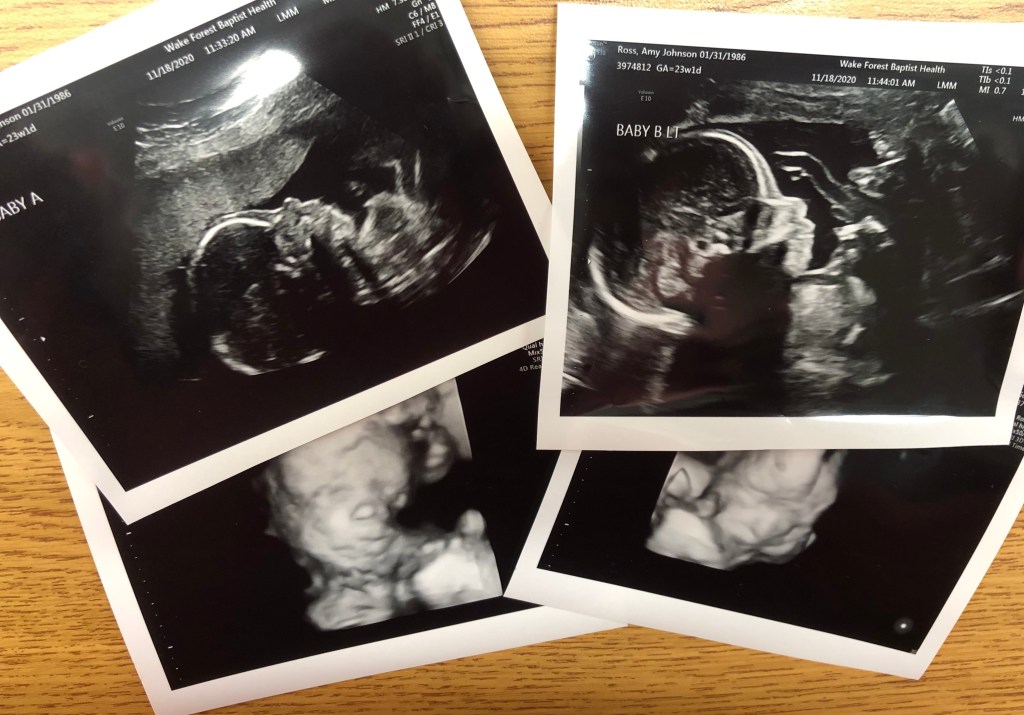

Today we had another ultrasound with our maternal fetal medicine. This ultrasound was focused on growth of the babies and not necessarily Baby A’s heart. From what I could see, and from the images we have been looking at up until this point, it looks like the left ventricle is still about the same size as the right. It is still critical aortic stenosis and the left side isn’t pumping as well, but I’m hoping there isn’t too much damage-causing change. Our next Fetal Echocardiogram is on December 3rd.

Both babies are growing very well and look great otherwise! Baby A is measuring around 1 lb. 3 oz. and Baby B is measuring at 1 lb. 2 oz.! They are precious to watch, so close together. It’s amazing that there are two babies, even now it is still hard to believe!